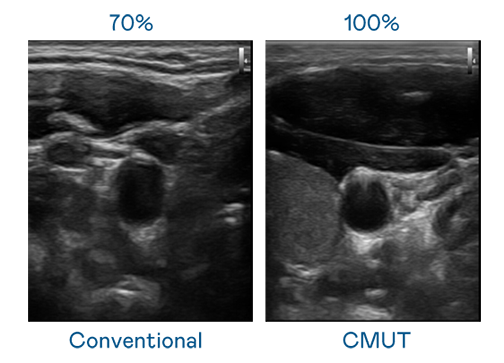

CMUT 技術是一種用電容式微機電元件來產生超音波訊號的技術。與傳統 PZT 壓電式技術相比,CMUT 頻寬增加 30%,更寬頻的超音波訊號讓影像解析度大幅提升,是實現高影像品質醫療超音波掃描、促進精準醫療發展的關鍵技術。

超音波影像的解析度高低,首先取決於探頭能發出的訊號頻寬。sunbet申搏 CMUT 可提供高清晰的超音波訊號,提供高頻寬、高靈敏度、影像紋理細節更高的超音波影像,協助醫護人員縮短影像判讀時間及利用精準的醫療影像進行診斷。